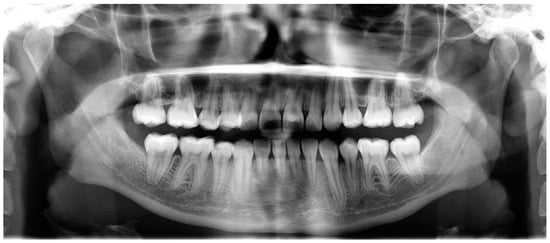

- Evaluation of impacted teeth, a common indication of CBCT in orthodontics. The advantages of CBCT include assessment of the tooth location and position, the stage of development, and status of adjacent teeth. CBCT is justified in these cases, because CBCT has the capability of evaluating the impacted teeth and adjacent structures more accurately than 2D conventional imaging. The benefit–risk ratio is favorable, especially if the CBCT volume is collimated to the impacted tooth. Figure 1, Figure 2, Figure 3 and Figure 4 show an example of impacted maxillary canines, and their proximity to the maxillary lateral incisors. Figure 1 shows an intraoral photograph. The benefit of CBCT acquisition in this case includes the ability to visualize the canines and the lateral incisors in three dimensions, which can be visualized in Figure 2 and Figure 3. In this case, the maxillary right lateral incisor exhibited external root resorption, a finding that would be difficult to see on a conventional 2D panoramic radiograph. Figure 4 shows a Maximum Intensity Projection of a panoramic view derived from the CBCT volume. This unique view is free of magnification, distortion, ghost images, and overlaps frequently seen in conventional 2D panoramic radiography.